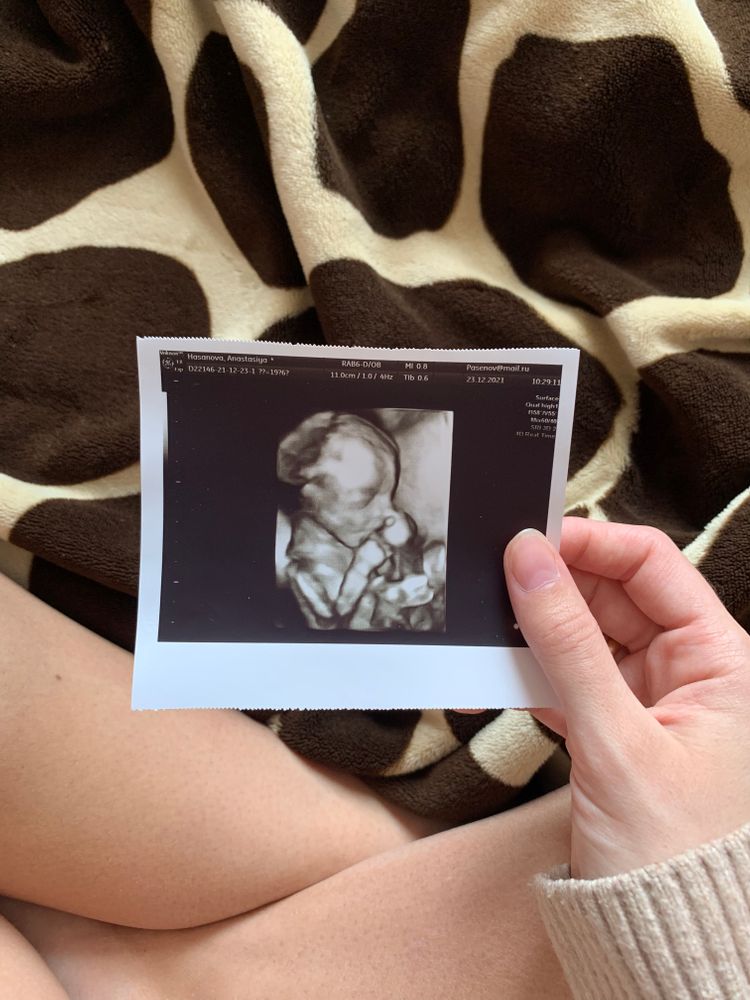

На каком сроке лучше делать 4D узи?

УЗИ, КТГ, доплерДевочки, на каком сроке лучше всего потратиться на 4d узи?)) в какое время малыши уже прям человеки?)) у меня сейчас 20 недель, хочу сходить, но начиталась отзывов, что на этом сроке детки ещё «страшненькие»😃🙈 если кто то делал примерно на моем сроке, поделитесь фоточками пожалуйста🥰 если хотите можно в личку)

На втором скрининге в 19+1 врач включила 4D, хороший человечек уже. Фото в дневнике у меня есть

Я ведусь платно, поэтому каждое узи есть вид в 4д. С 20 недели очень милые фотки) Но если вам отдельно придётся за это доплачивать, то лучше после 22-24.

26-28 недель самое хорошее время, как говорят сами узисты. Нам узист при каждом визите делала, конечно, самые большие щёчки в 32 недели)

Все скрининги и УЗИ проходила в самарской школе ультразвука. На каждом обследовании делали 4D. В 26-28 нед самые лучшие фотки, у малыша уже щечки пухленькие. На более позднем сроке малыш с трудом помещается в экран. В 20 нед еще похож на инопланетянина))))

В 20.0 ровно по мес (20.2 по узи) включали на скрининге 3-4д режим, был такой)